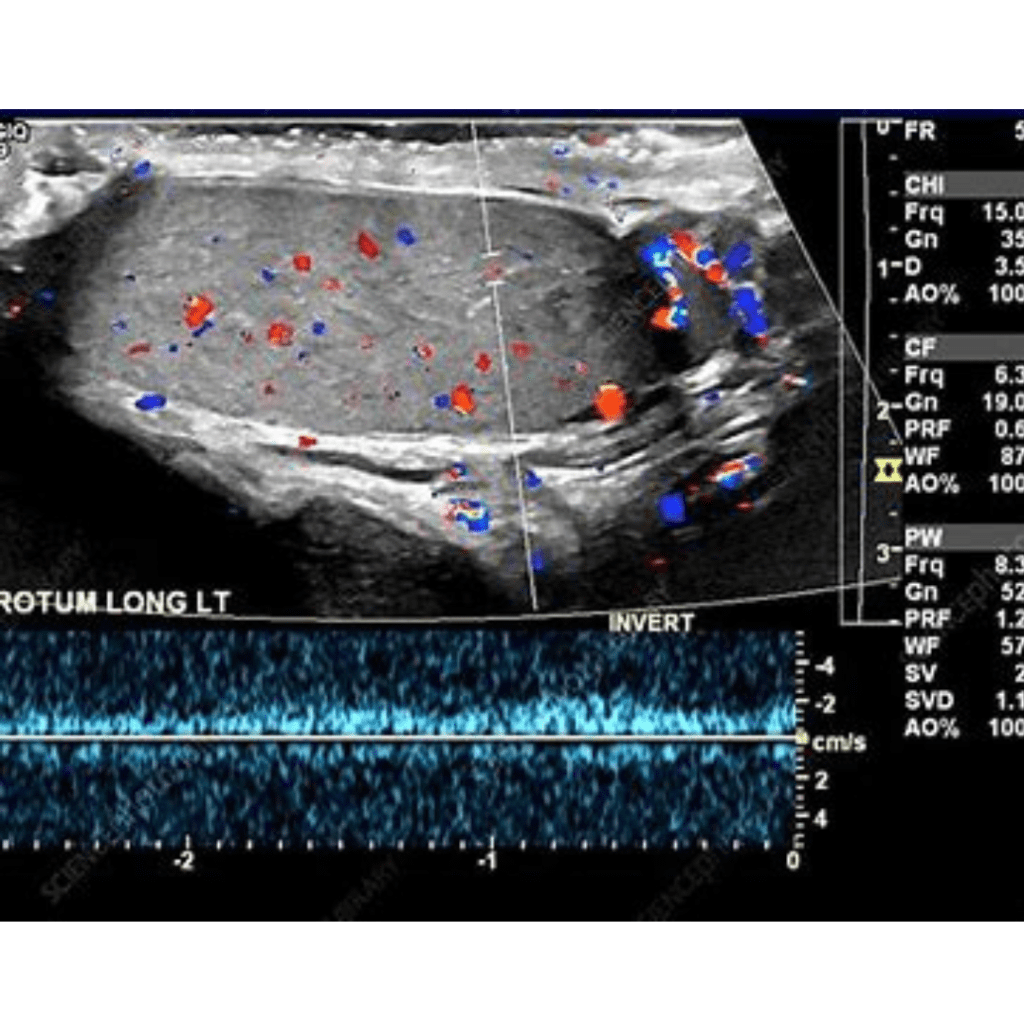

A testicular ultrasound is a non-invasive procedure that uses sound waves to create images of the testicles and surrounding structures in the scrotum. It is used to evaluate testicular masses, pain, swelling, or trauma.